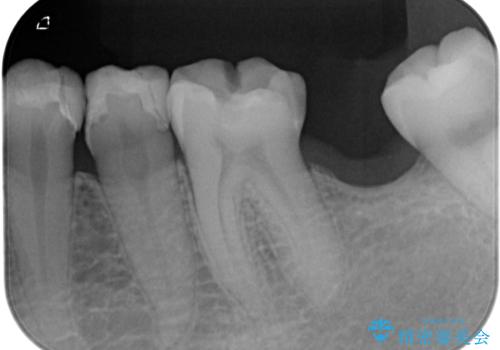

- 詰め物が外れかけているのでやり替えたいとのことで来院された患者様です。来院時に詰め物の不適合を認めたので歯髄診を行い歯髄の生活反応を確認できたので、フルジルコニアクラウン、セラミックインレー修復を行っていくことにしました。

拡大鏡視野下で、コンポジットレジン、虫歯の除去を行い、フルジルコニアクラウン、セラミックインレーに適した形に整えました。